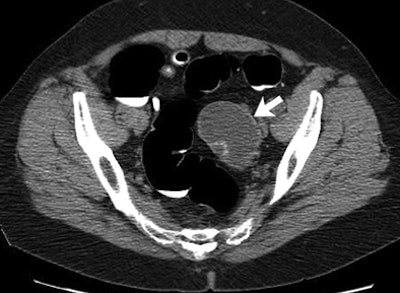

![]() |

| Adnexal pathologic findings (arrow) identified at routine CTC screening and surgically removed after further workup include mucinous cystadenoma. Image republished with permission of the Radiology Society of North America from Radiology, October 2010, Vol. 257:1, pp. 144-150. |